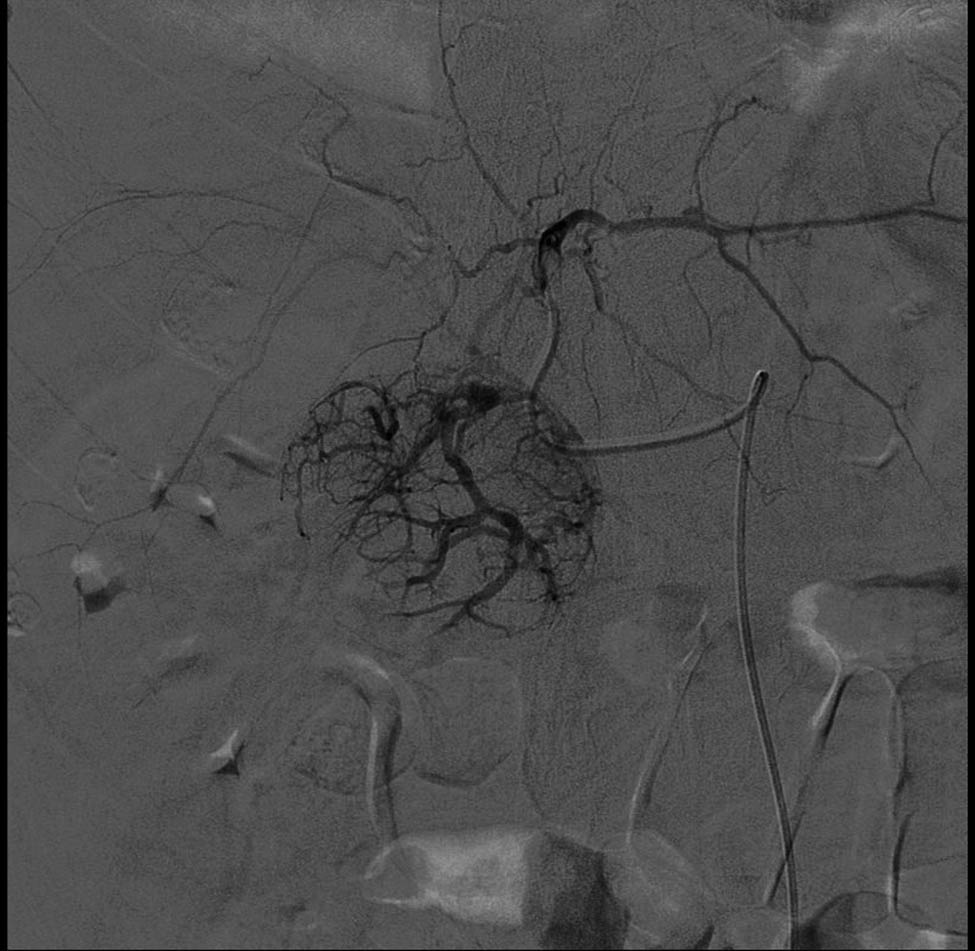

The angiographic examination was performed, with right transfemoral arterial approach, and showed an expansive lesion of the IV hepatic segment, a source of active intra-abdominal bleeding (Figure 2).

Expansive lesion of the IV hepatic segment.